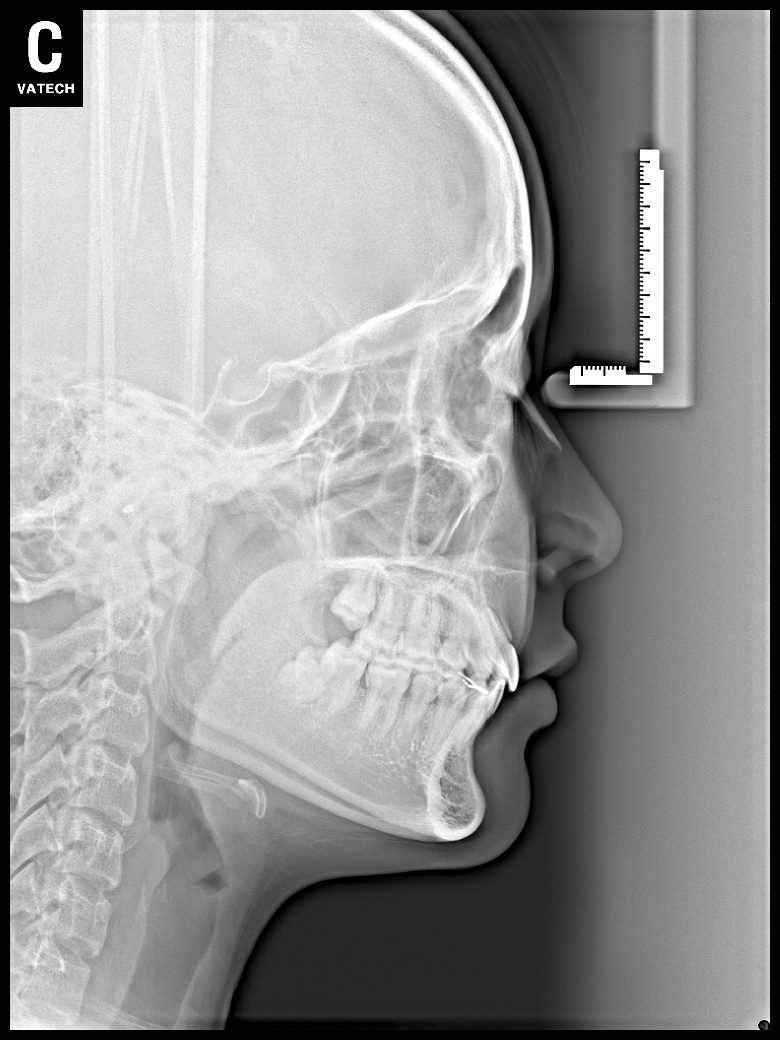

치료 후 사진입니다.